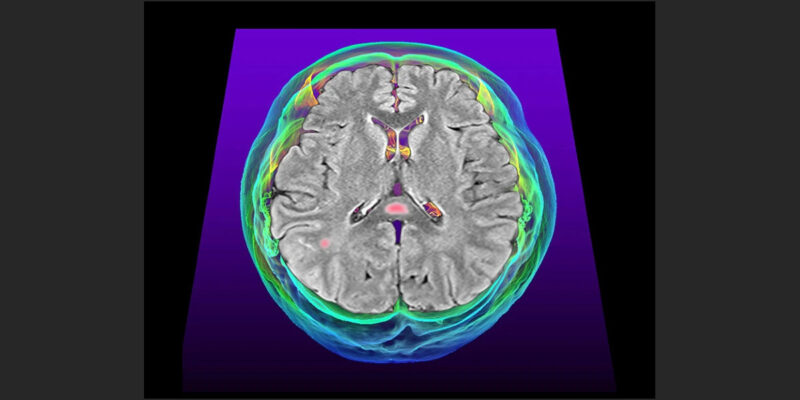

Koku kaybı, baş ağrıları, hafıza sorunları: COVID-19, günlük işleri zorlaştıran rahatsız edici bir nörolojik semptom fırtınasına neden olabilir. Yeni araştırmalar bu semptomların altında beyindeki inflamasyonun yatabileceğine dair kanıtlar sunuyor.

Tüm veriler aynı yönü göstermiyor. Bazı yeni çalışmalar, COVID-19’a neden olan SARS-CoV-2 virusunun doğrudan beyin hücrelerini infekte ettiğini öne sürüyor. Bu bulgular, COVID-19 ile ilişkili beyin sorunlarına doğrudan infeksiyonun yol açtığı hipotezini destekliyor. Beyindeki inflamasyonun anahtar olduğu fikri ise yeni bir destek kazandı: bir çalışma COVID-19’lu kişilerde belirli beyin bölgelerinin inflamasyona yatkın olduğunu saptadı.

Araştırmacılar, COVID-19’un neden olduğu beyin sorunlarının suçlusunu aramaya başladığında, inflamasyon hızla başlıca şüphelilerden biri oldu. Bunun nedeni, vücudun davetsiz misafirlere karşı salgıladığı bağışıklık hücreleri ve kimyasallara bağlı inflamasyonun, HIV gibi başka virusların neden olduğu bilişsel semptomlarla bağlantılı olmasıdır. SARS-CoV-2 vücutta güçlü bir bağışıklık tepkisine yol açar, ancak beyin hücrelerinin bu tepkiye katkıda bulunup bulunmadığı ve eğer öyleyse nasıl olduğu belirsizdi.

Charité – Berlin Üniversitesi Tıp Fakültesi’nden nöropatolog Helena Radbruch ve meslektaşları, COVID-19’dan ölen insanlardan alınan beyin örneklerini inceledi. SARS-CoV-2 ile infekte olmuş herhangi bir hücre bulamadılar. Ancak bu insanların belirli beyin bölgelerinde, diğer nedenlerden ölen insanlara göre daha fazla bağışıklık aktivitesi olduğunu saptadılar. Bu olağandışı aktivite, koku alma duyusuyla ilgili olan koku alma soğanı ve nefes alma gibi bazı bedensel işlevleri kontrol eden beyin sapı gibi bölgelerde fark edildi. Bu durum yalnızca virusa yakalandıktan kısa süre sonra ölen insanların beyinlerinde görüldü.

Radbruch’a göre bu gözlemler, COVID-19’un beyin dışında neden olduğu iltihaplanmanın infeksiyonun erken dönemlerinde belirli beyin bölgelerinde bağışıklık tepkisini tetiklediğini ve bunun da nörolojik semptomlara yol açabileceğini akla getiriyor. Ekip, nöroinflamasyonun devam etmesi durumunda, infeksiyondan sonra aylarca veya yıllarca sürebilen karmaşık semptomlar topluluğu olan uzun COVID ile bağlantılı beyin semptomlarına yol açabileceğinden şüpheleniyor. Bulgular Nature Neuroscience dergisinde yayımlandı.